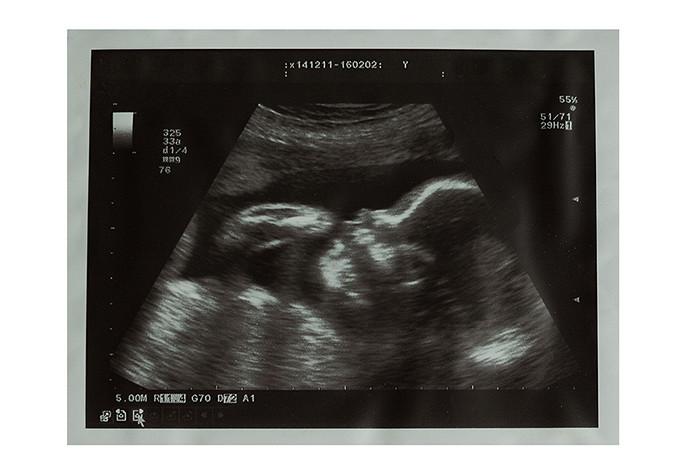

Содержание статьи Что показывает фото ультразвукового исследования по неделям беременности? Фото УЗИ ребенка на 23-24 неделе беременности

Что происходит на 24 неделе беременности с малышом и мамой: фото живота и УЗИ плода, ощущения женщины, развитие ребенка . Узнайте о том, сколько должно быть шевелений и что нужно знать беременной двойней на сроке в двадцать четыре недели .